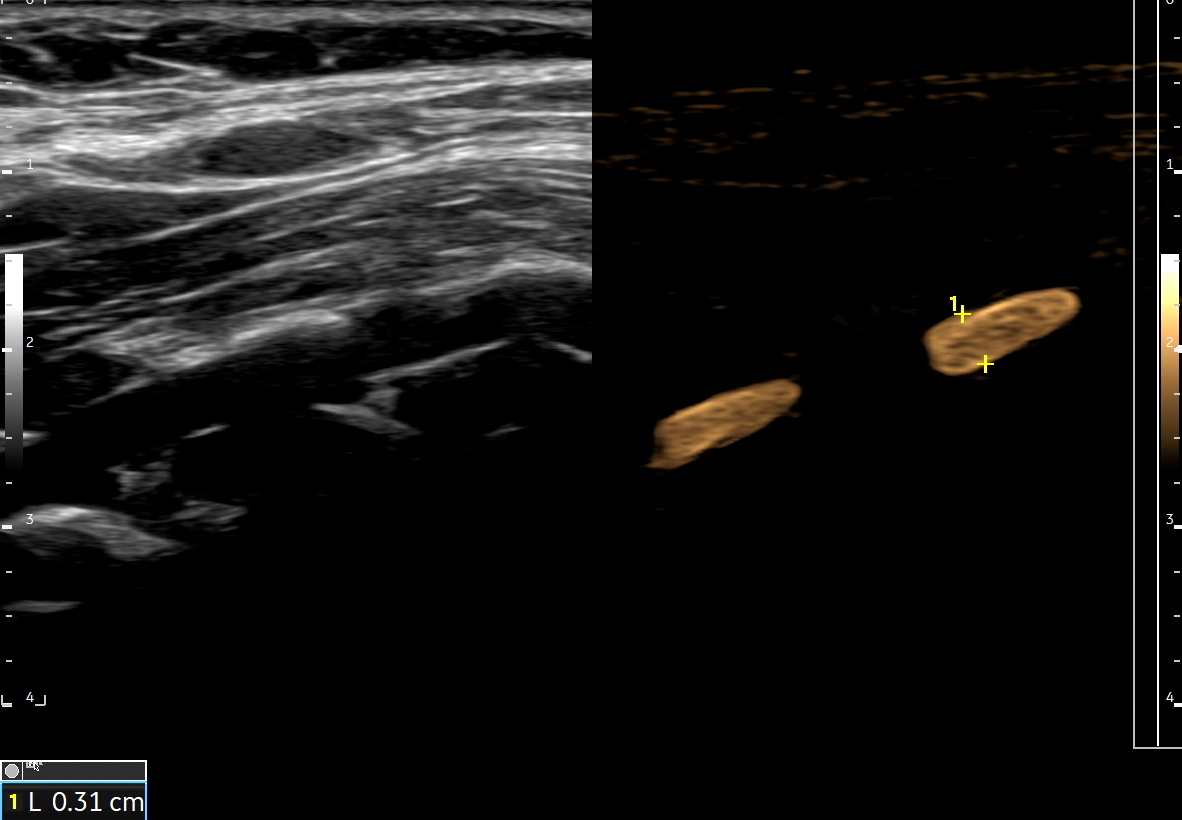

Tryb B-flow to modalność obrazowania w ultrasonografii, która dostępna jest w aparatach firmy GE. Oparta jest o technologię polegającą na selektywnym wzmacnianiu sygnału poruszającego się obiektu i jednoczesnej supresji sygnału z obiektów stacjonarnych. W związku z powyższym metoda może być wykorzystywana do obrazowania płynącej krwi, zarówno w naczyniach dużych, jak i w naczyniach mikrokrążenia, a także poruszających się tkanek i materiałów litych.

Tryb B-flow wyjątkowo korzystnie sprawdza się także przy badaniu wnętrza dużych i średnich naczyń. Otóż umożliwia on pewne zobrazowanie drożności naczynia, umożliwia wykazanie obecności / lokalizacji naczynia przy niesprzyjających warunkach obrazowania w trybie B, a poza tym uzyskiwane w omawianym trybie obrazy zarysów błony wewnętrznej naczyń (np. tętniczych blaszek miażdżycowych, skrzeplin przyściennych, zmian w przebiegu dysplazji włóknisto-mięśniowej, czy zapaleń tętnic) charakteryzują się wysoką rozdzielczością i kontrastowością. Skany dużych naczyń w trybie B-flow przypominają wręcz te uzyskiwane w klasycznej angiografii opartej o promieniowanie rentgenowskie. B-flow wykorzystywany może być praktycznie i rutynowo do obrazowania naczyń szyi i kończyn, naczyń wątroby, naczyń trzewnych, nerkowych oraz dużych naczyń brzusznych.